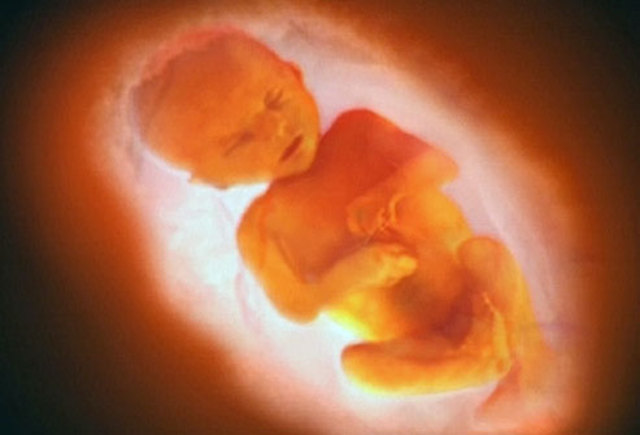

• Period: to

Length and Weight in Month 5

The baby is about 6.5 inches long from head to rump and weighs almost 11 ounces. From head to heel, the baby is about 10 inches.

• Baby's Senses

Baby's Senses

The baby can detect a mumbled version of your voice at around this time. It may shift or kick a little in response.